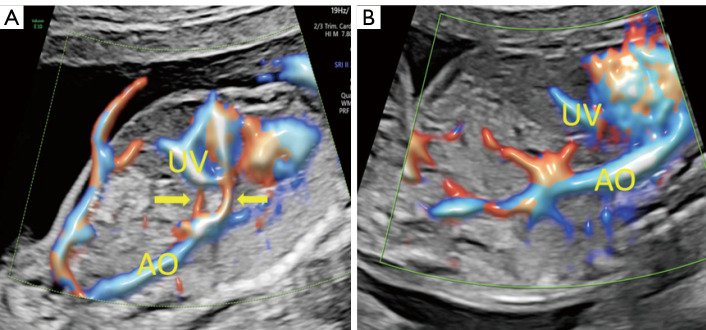

Prenatal diagnosis of abdominal aorta-umbilical vein fistula using high-definition flow render mode and spatiotemporal image correlation.

应用高清血流渲染模式和时空图像相关技术产前诊断腹主动脉-脐静脉瘘。